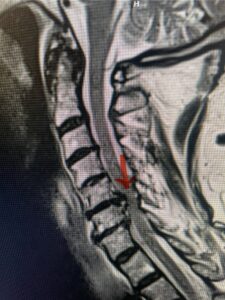

Fig. 7a Sagittal and axial T2-weighted cervical MRI’s demonstrating spinal cord compression slightly to the left secondary to disc/osteophyte complex (red arrow)

Fig. 7b

The case illustrates a more subtle finding of cervical myelopathy in a young 52 year-old male who presents with 5 months of left upper extremity weakness and burning. He also had developed over the last two months pain in his right upper extremity. He also had difficulty with fine motor skills. He had a positive Hoffman reflex and mild 4-4+ long tract weakness of his left arm and leg. Cervical MRI revealed an explanation for the patient’s symptoms (Fig. 7) as it revealed a disc osteophyte complex causing some cord flattening, slightly more to the left. We performed a C5-6 anterior cervical discectomy and interbody fusion with cage and plate (Fig. 8) He had a significant improvement in his weakness, numbness, and pain. What is interesting is that this was a relatively young patient without severe cord compression but was significantly affected by a mild amount of cord compression. This may speak to how a younger spinal cord may react much more adversely perhaps secondary to a less compliant spinal cord.